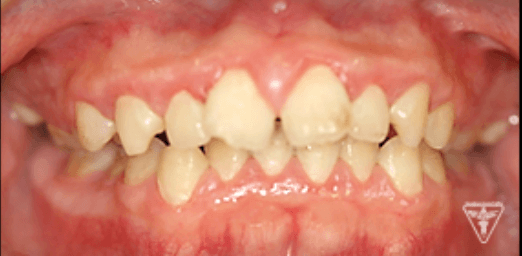

治療前

10代女性:矯正治療

治療前後の比較